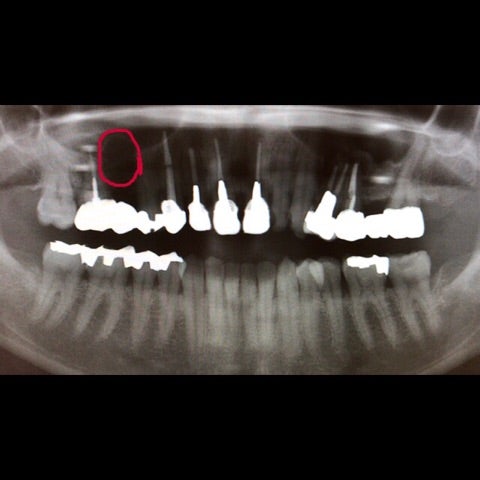

「数年前から右上の歯に違和感があり、かかりつけの歯医者で歯の治療を繰り返していたが違和感が消えない。」

▶︎それよりも私がまず気になったのは赤いラインで引いた丸い透過像でした。続いて精査するためにCT撮影を行いました。